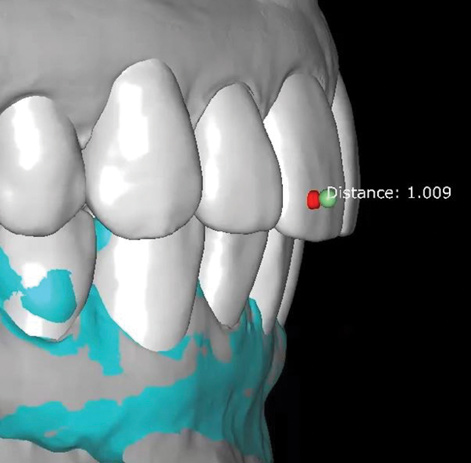

Fig 8. Scans are used to mock-up desired restorative results using modeling software. The teal-green areas represent the current tooth form, and the white areas show the desired or digital wax-up. A reduction of 1.009 mm was required prior to preparation, making endodontic treatment likely if orthodontic treatment is not considered.

Figure 8

Fig 9. Scans are used to mock-up desired restorative results using modeling software. The teal-green areas represent the current tooth form, and the white areas show the desired or digital wax-up. A reduction of 1.009 mm was required prior to preparation, making endodontic treatment likely if orthodontic treatment is not considered.

Figure 9